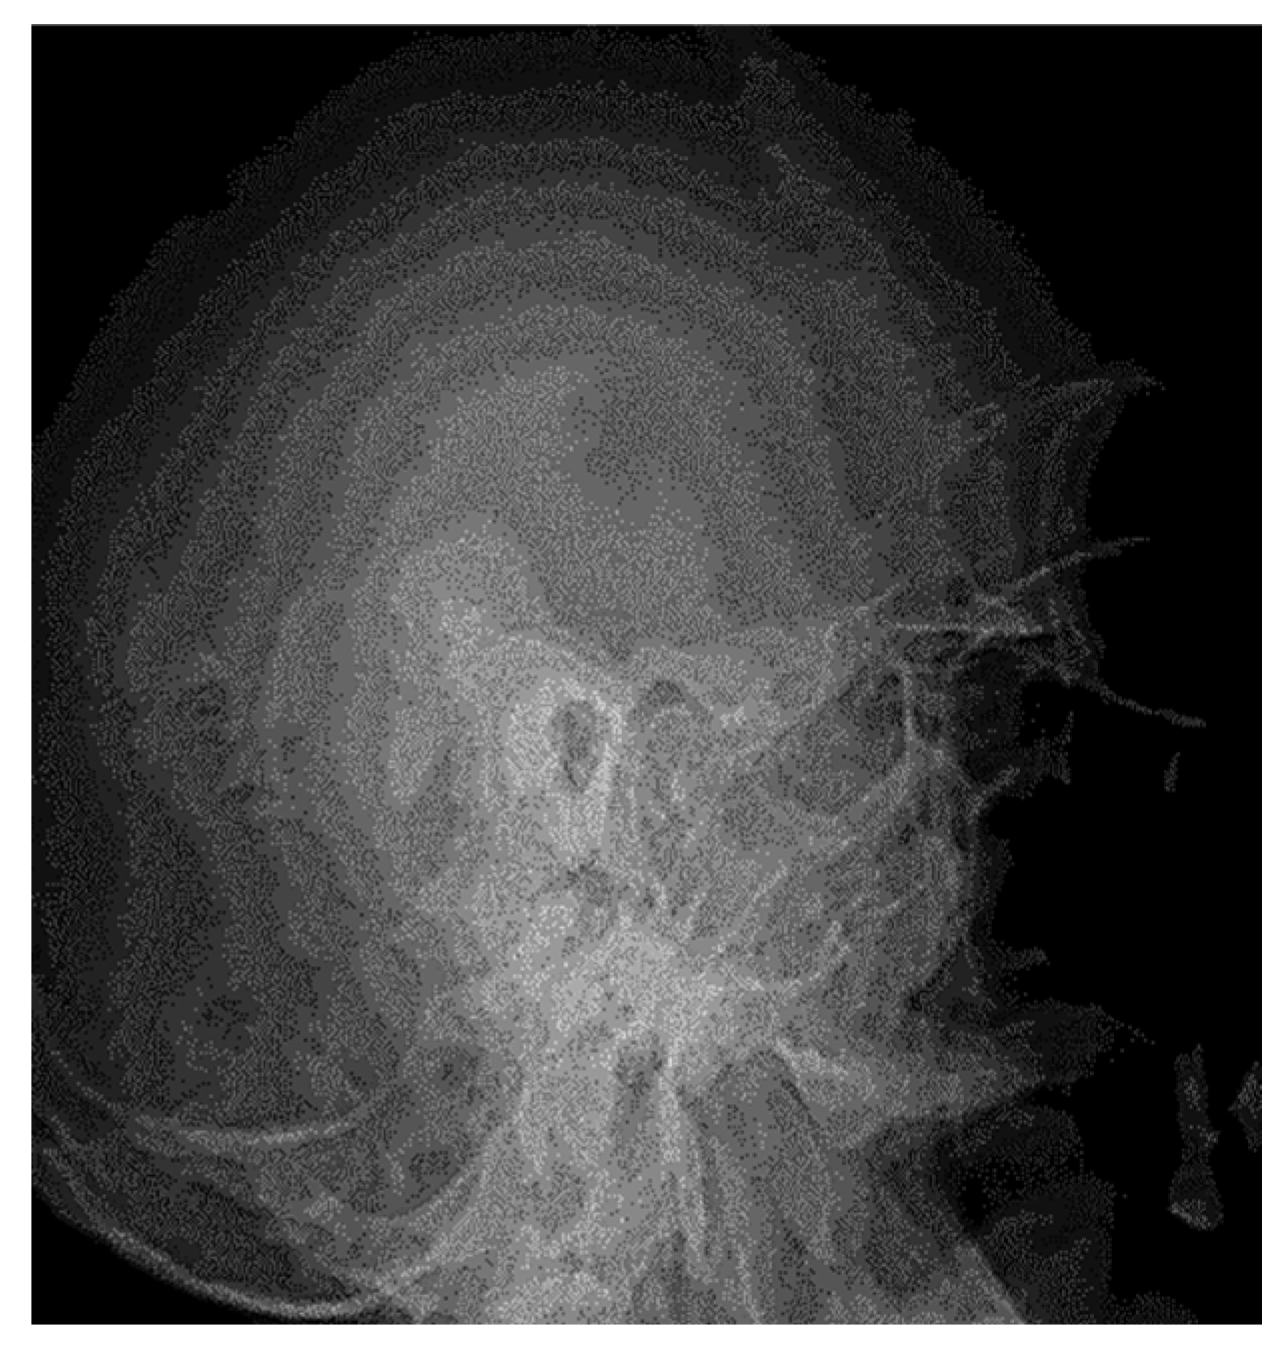

3.1.1. Conventional Radiology

3.1.2. Computed Tomography and Magnetic Resonance Imaging